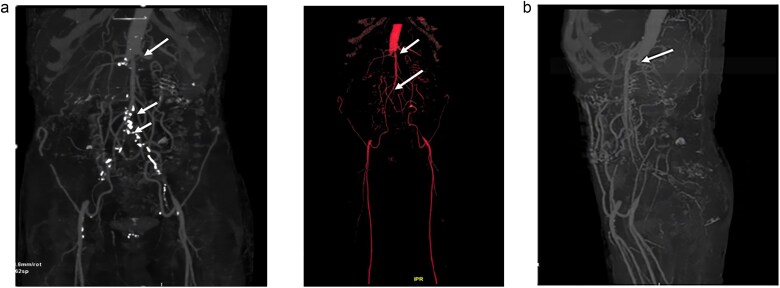

Lerich综合征,又称主动脉-髂闭塞综合征,是下肢闭塞性动脉病变中的一种特殊疾病,定义为主动脉-髂连接处血栓性闭塞。我们报告一例60岁的高血压病患者,慢性吸烟者。他入院接受肾功能衰竭评估,确诊为慢性肾病。此外,由于肾脏超声显示肾脏不对称(4,9 cm),要求行CT血管造影,确诊为肾动脉狭窄的Lerich综合征。进行了包括病因学在内的补充评估,未发现异常。治疗上,患者接受间歇性血液透析和治疗性抗凝治疗。我们的病例是莱里奇综合征罕见而偶然的发现。

Lerich syndrome, also known as aorto-iliac obliteration syndrome, is a specific entity among obliterative arteriopathies of the lower limbs, is defined as thrombotic occlusion of the aorto-iliac junction. We report a case of 60-yearold patient, chronic smoker with hypertension disease. He was admitted for an assessment of renal failure, in whom the diagnosis of chronic kidney disease was confirmed. Moreover, in the presence of renal asymmetry (4,9 cm) on renal ultrasound, a CT angiography was requested, confirming the diagnosis of Lerich syndrome with renal artery stenosis. A complementary assessment, including etiological one was performed, revealing no abnormalities. Therapeutically, the patient was placed on intermittent hemodialysis and curative anticoagulation. Our case represents a rare and fortuitous discovery of Lerich syndrome.